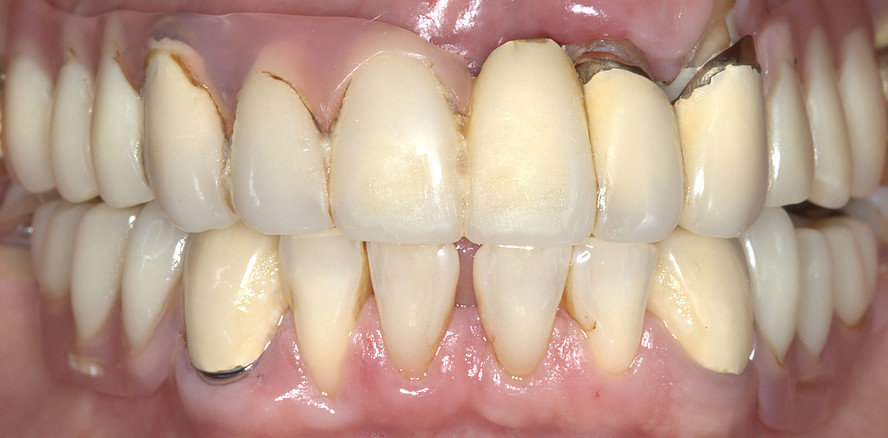

Ein 62-jähriger Patient stellte sich mit bestehendem Zahnersatz im Oberkiefer vor und äußerte den Wunsch nach einer implantatprothetischen Versorgung. Drei Restzähne im Oberkiefer waren erhaltungswürdig. Nach differenzialdiagnostischer Analyse wurde eine abnehmbare, teleskopierende Versorgung geplant. Die Zähne 17 und 27 wurden mit provisorischen Kronen aus Polymethylmethacrylat (PMMA) versorgt, spielten jedoch keine tragende Rolle in der Gesamtplanung.

Nach strategischer Pfeilervermehrung zur polygonalen Abstützung wurden vier Pfeiler für die geplante Prothesenspanne definiert. Die Versorgung begann mit vorbereitenden Maßnahmen wie einem digitalen Mock-up zur Bestimmung der horizontalen und vertikalen Kieferrelation (Abb. 1 + 2).

Eingliederung der Reise- und Definitivprothese

Nach Verkleben der sekundären Galvanokappen mit dem Tertiärgerüst verbleiben die Primärzirkonkappen im Mund. Um dem Patienten auf Basis dieser Pfeiler eine Interimsversorgung geben zu können, wird eine sogenannte Reiseprothese mit der Ästhetik und Funktion der finalen Versorgung hergestellt, welche auch als Referenz hierfür dient (Abb. 18+19).

Die definitive Prothese konnte im dritten Behandlungstermin problemlos eingegliedert werden. Es waren lediglich minimale okklusale Anpassungen erforderlich (Abb. 20–24).